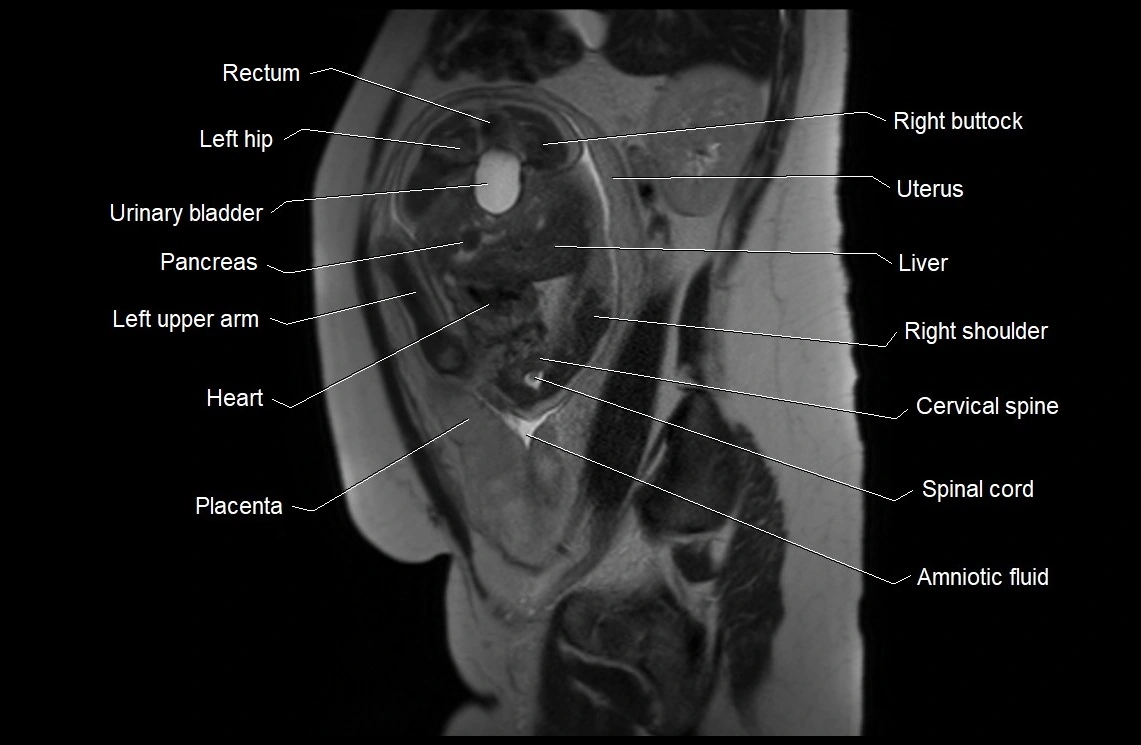

Amniotic fluid is the protective liquid surrounding the fetus within the amniotic sac. It plays an essential role in cushioning the fetus, enabling fetal movement, maintaining temperature stability, and allowing for normal lung and musculoskeletal development.

The volume and composition of amniotic fluid change throughout pregnancy. It is mainly derived from maternal plasma in early pregnancy, while in later stages, it consists largely of fetal urine, lung secretions, and transmembrane exchanges.

• Imaging relevance: MRI used for fetal visualization and assessing oligohydramnios/polyhydramnios when ultrasound is inconclusive

MRI Appearance

T2 HASTE (T2 GRE):

• Amniotic fluid shows very bright hyperintense signal

• Provides natural contrast against fetus and placenta

• Small particles (vernix) may appear as scattered hypointense foci within bright fluid

T1 GRE:

• Amniotic fluid shows low signal intensity (dark)

• Hemorrhage, infection, or proteinaceous content may cause focal or diffuse high signal intensity